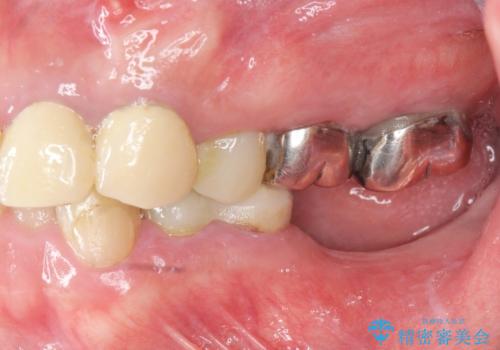

[ 失った歯の機能を回復 ] 奥歯のインプラント治療